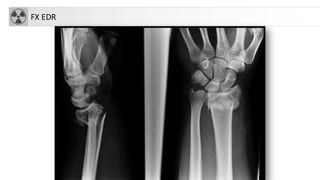

FX EDR

FRACTURASDE MUÑECA • 17%de fracturas atendidas en urgencias (1/4 del total de fracturas) • Más frecuente mujeres y osteoporosis • FX Colles. Criterio: fractura de extremo distal de radio con angulación dorsal y acortamiento radial, que produce la típica deformidad en dorso de tenedor • FX extremidad distal de radio (si no cumple criterios anteriores). • Otras FX: Smith, Barton, Hutchinson… • Genéricamente: FX EDR